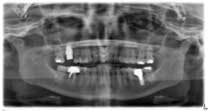

An 81-year-old female with stent placement 10 years ago taking no medications presented with a chief complaint that her old prosthesis broke, and she cannot chew and function. She had a previous bridge consisting of an implant in the No. 1 site combined with the natural teeth and implants in the 8, 9, 14, 15. No. 8, 9 implants were malpositioned with a 35-degree angle and significant mucogingival defects.

Various treatment options were explained to the patient, and a treatment plan consisting of Coldwell-Luc external sinus lift with bilateral block placement in area 5 to 7 and 10 to 12 was agreed upon.

Under local anesthesia, a full thickness flap was elevated from the upper right to upper left posterior segments. Using a piezoelectric handpiece, a buccal window hinge osteotomy was elevated in the maxillary right posterior region. A mixture of DFDBA, anorganic bovine bone, and PRF was placed. A collagen membrane was used to cover the buccal window. Simultaneously, two puros J-block allografts were secured in the 5 to 7 and 10 to 12 region with stainless steel screws (1.6 x 8 mm screws). A mixture of DFDBA, anorganic bovine bone and PRF was placed over each area and covered with PRF sheet and a collagen membrane. Primary closure was obtained with CV-5 Goretex sutures. Healing was uneventful. After six months of healing, six straight implants were placed in sites 3, 4, 5, 6, 11, and 12. Healing abutments were placed at stage I. Healing was uneventful. After four months of healing, six custom abutments were fabricated by his dentist and cover screws were placed on implants 8 and 9 and converted into pontics.

Removing the implants would have created a large buccal defect, which would have created elongated pontics in the maxillary anterior region. The prosthesis was completed, and the patient is stable and highly appreciative of her ability to smile and chew.

Case 2: Sinus lift, bone graft, PRP, and after healing implant placement